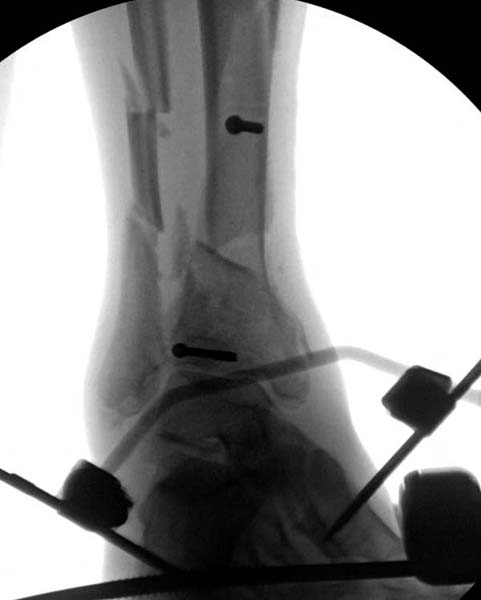

Современную тактику лечения переломов пилона описали коллеги, а мне остается подтвердить клинически. В многоэтапном лечении главное - это предупреждение сокращения мягких тканей, от которого зависит судьба конечности. Дистракция любым наружным фиксатором, и по готовности мягких тканей - премежуточная или окончательная фиксация.

В нашем случае, травма в результате коллапса крыши. Открытый перелом. Ургентные Irrigation and Debridment, дистракция наружным фиксатором. В госпиталях первого уровня редко бывает изолированная травма, и на другой стороне повреждение стопы с переломом навикулярной кости. После обработки раны - вакуум и двухсторонние наружные фиксаторы.

Через три дня повторная I&D, где через рану манипулировали дистальным фрагментом с установкой пары межфрагментарных шурупов. На рану вакуум и следующая обработка закончилась закрытием раны. Отек держался немного дольше, чем обычно.